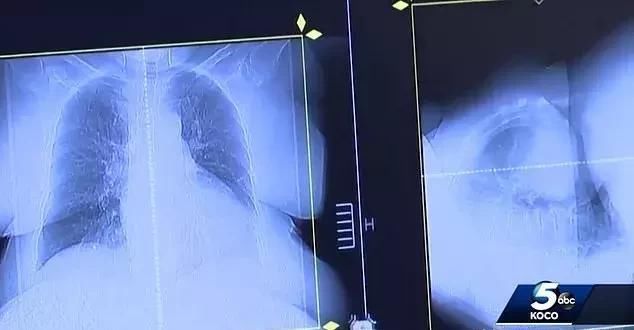

提彭斯于2017年9月再次去医院做扫描,报告再次显示没有任何癌细胞。提彭斯这时才告诉医师们自己偷偷服用 狗药 。虽然没有办法证明驱虫治疗对

提彭斯于2017年9月再次去医院做扫描,报告再次显示没有任何癌细胞。提彭斯这时才告诉医师们自己偷偷服用“狗药”。虽然没有办法证明驱虫治疗